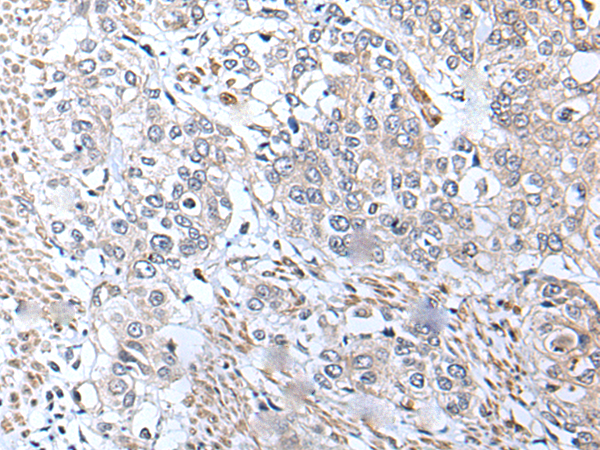

Applications:

ELISA, IHC

IHC positive control:

Human brain and human prostate cancer

IHC Recommend dilution:

30-150